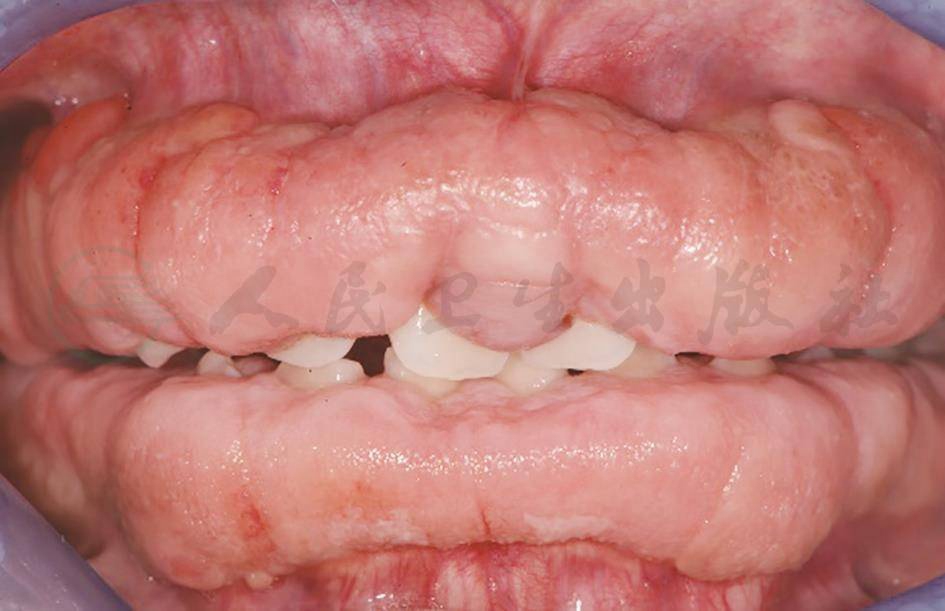

牙龈开始纤维增生可在乳牙萌出时、恒前牙萌出时或恒后牙萌出时,一般开始于恒牙萌出之后,牙龈逐渐增生,可累及全口的牙龈缘、龈乳头和附着龈,甚至达膜龈联合处,但不影响牙槽黏膜。增生的牙龈组织致密而硬,色泽比正常略白(图4)。增生的范围可呈局限性,也可呈广泛性。增生通常为对称性,也有单侧的增生。一般下颌症状轻于上颌,上颌磨牙区、上颌结节部及下颌磨牙区的病变,均为舌腭侧比颊侧明显,其中以上颌磨牙腭侧最为严重。

图4患儿,女,13岁,遗传性牙龈纤维瘤病

(北京大学口腔医学院葛立宏医师提供)